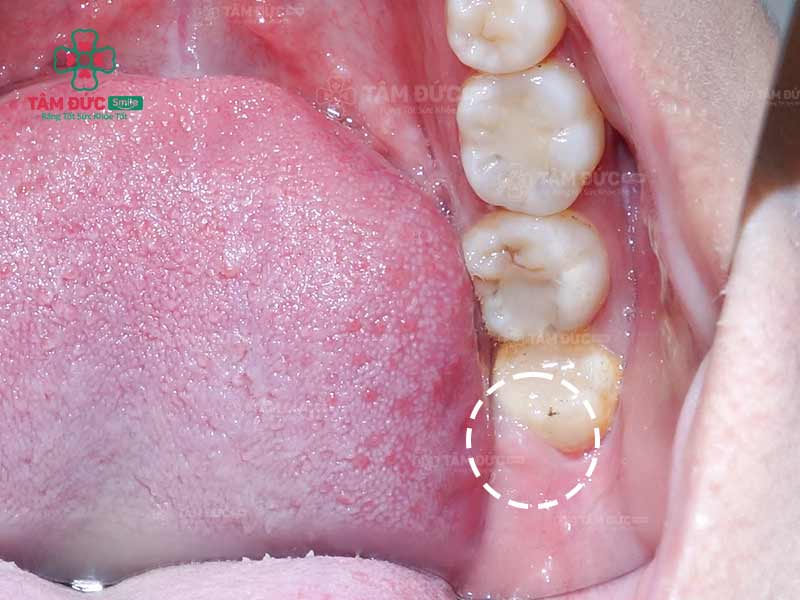

2.1. Nướu sưng đỏ, sờ vào có cảm giác đau và cứng

Răng khôn không thể mọc lên sẽ chèn ép các dây thần kinh bên dưới hàm. Tình trạng này thường dẫn đến đau và sưng liên tục, có thể tái phát nhiều lần. Sau thời gian dài nếu Quý khách vẫn chưa thấy răng mọc lên, thì răng khôn đó đang mọc ngầm.

Răng khôn mọc ngầm làm sưng nướu